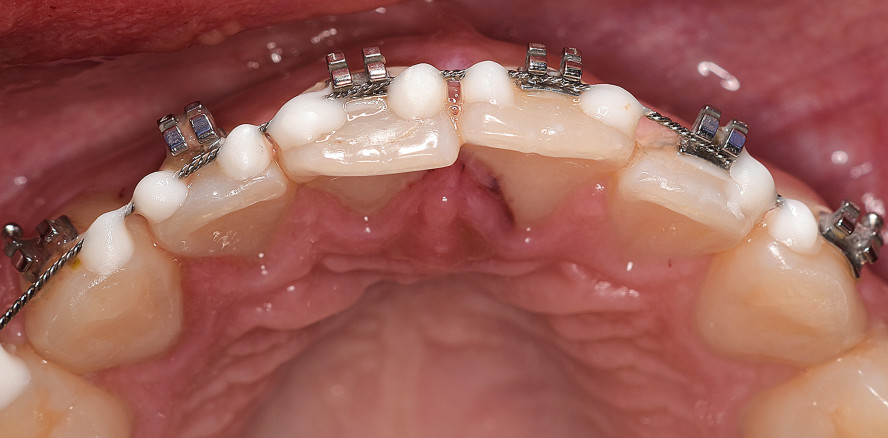

Im Rahmen der Erstvorstellung wurde eine Weichteilverletzung im Bereich der Oberlippe festgestellt, welche durch den diensthabenden Chirurgen versorgt wurde (Abb. 1a–d). Bei genauer Inspektion der Zähne war eine Dislokation der Zähne 12 und 11 um circa 1–2 mm nach palatinal erkennbar. Darüber hinaus war eine deutliche Blutung aus dem Sulkus beider Zähne zu erkennen, die Zähne 12 und 11 waren trotz der Multibandstabilisation gelockert (Lockerungsgrad I). Beide Zähne waren am Unfallabend stark perkussionsempfindlich und reagierten nicht auf einen Sensibilitätstest.

Nach der Anfertigung einer Einzelzahnaufnahme Regio 13–11 am Unfallabend (Abb. 2a) wurden die Zähne im Bereich des Drahtes der Multibandapparatur zusätzlich mittels Säure-Ätz-Technik geschient und die Patientin antibiotisch mittels Doxycyclin zur Resorptionsprophylaxe abgeschirmt (100 mg, 1–0–1 für zehn Tage). Besonders nach schwerwiegenden Dislokationsverletzungen kommt der systemischen antiresorptiven Wirkung von Doxycyclin eine entscheidende Bedeutung zu.1 Mögliche Risiken und Spätfolgen des Frontzahntraumas wurden Vater und Tochter erläutert, zur Nachsorge stellte sich die Patientin am nächsten Tag erneut vor.

Einen Tag nach dem Unfall wurden zusätzliche Röntgenbilder angefertigt (Abb. 2b und c) und die suffiziente Schienung und Repositionierung der Zähne 12 und 11 dokumentiert. Die Zähne waren so weit beschwerdefrei, die durch die Dislokation geschädigten Zähne 12 und 11 reagierten nicht auf den Sensibilitätstest mit CO2-Schnee.

Nach weiteren fünf Tagen stellte sich die Patientin erneut vor. Die Schienung bzw. Multibandapparatur war zwischenzeitlich vom Kieferorthopäden entfernt worden. Die Zähne 12 und 11 reagierten nicht auf den Sensibilitätstest. Zusätzlich war nun an Zahn 12 eine deutliche Graufärbung zu erkennen, ein eindeutiges Zeichen für eine Pulpanekrose und zerfallene Blutbestandteile, welche sich in die Dentinkanälchen einlagern (Abb. 3a und b). Somit war eine endodontische Therapie des Zahns 12 dringend indiziert.